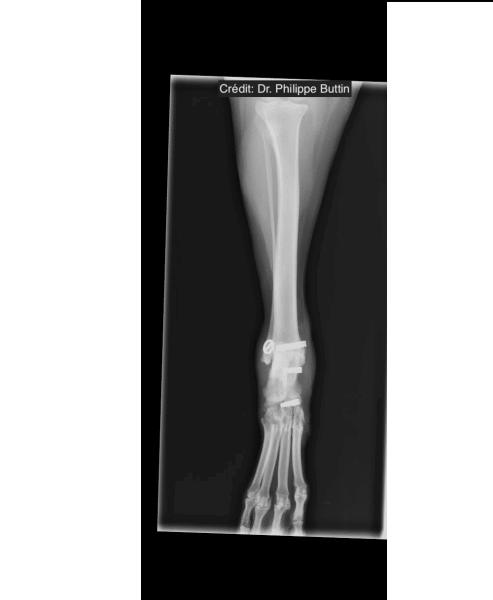

Reconstruction of tarsal medial collateral ligament

Radiologické snímky

Achilles Tendon Repair